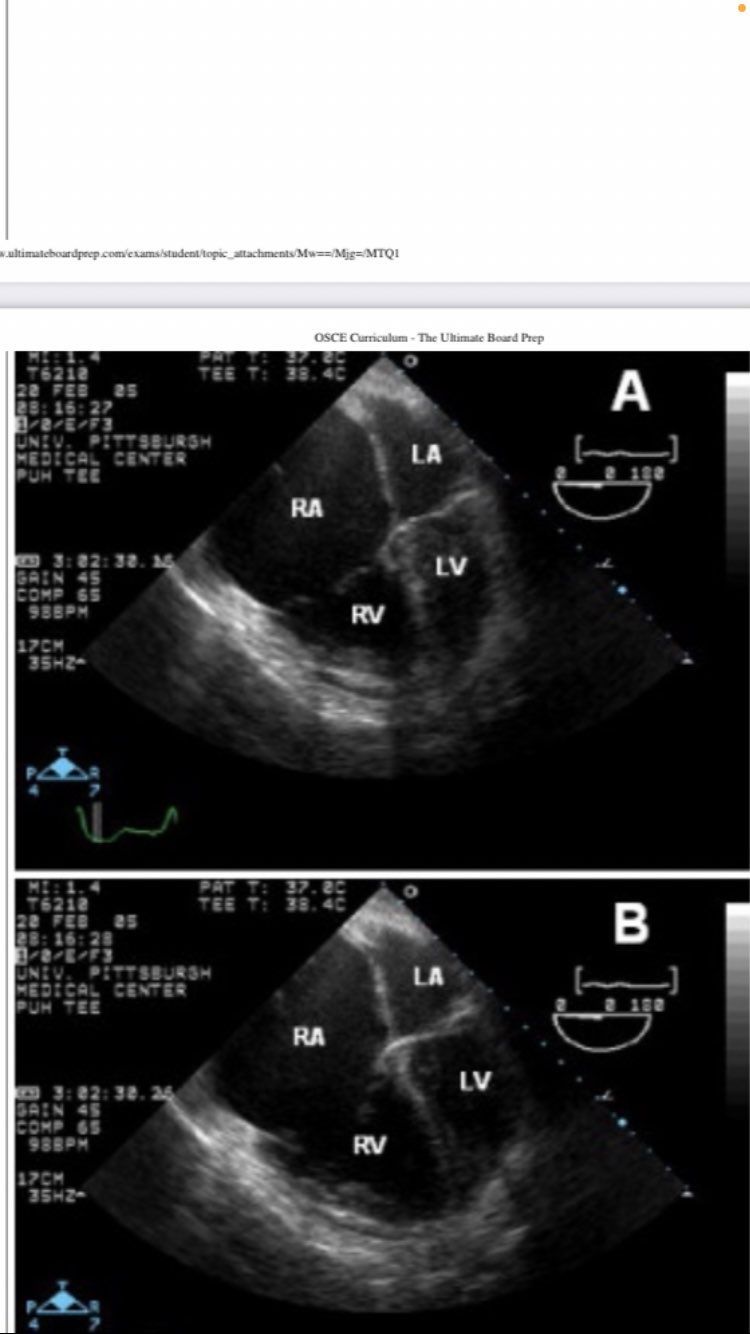

midesophageal 4 chamber

Midesophageal 4 chamber view